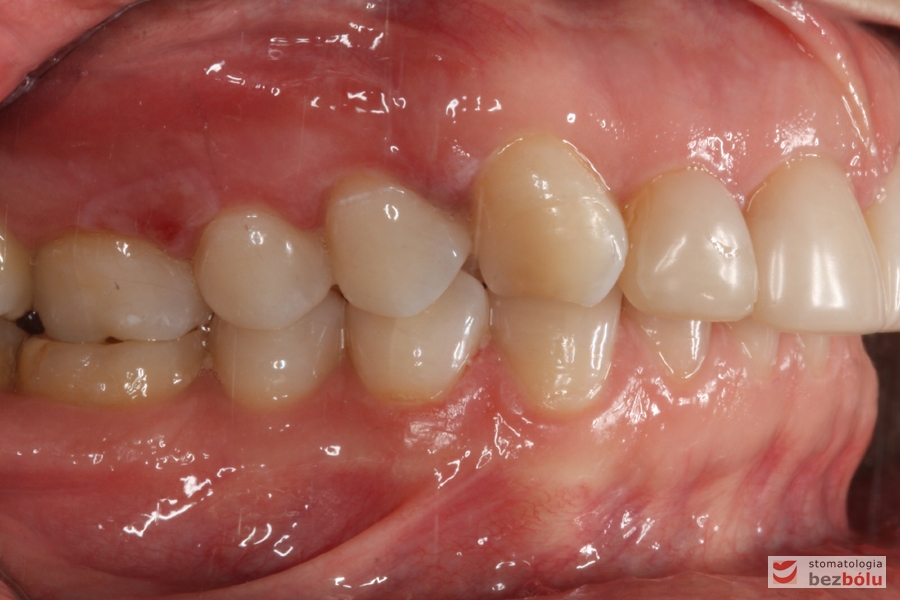

Zęby w zgryzie - strona prawa, II klasa kłowa i Angle'a, mezjalna inklinacja kła

Zęby w zgryzie – strona prawa, II klasa kłowa i Angle’a, mezjalna inklinacja kła